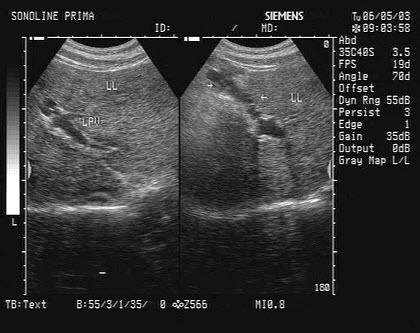

肝实质回声增粗,弥漫性病变,表示已经有肝硬化或肝纤维化吗?

相信肝病朋友们都在在彩超上看过肝实质回声增粗增强的描述,其实这是

肝实质回声光点细腻,分布均匀,肝胆胰脾未见异常:正常报告; 2.

肝实质回声异常 正常的肝脏回声是均匀的,没有异常回声,如果出现高,低

3,肝实质变化,由于肝内脂肪变性及纤维性变,肝实质内回声致密,回声

大结节性肝硬化肝实质内可见不规则反射带或脐带的弥漫性改变,结节性